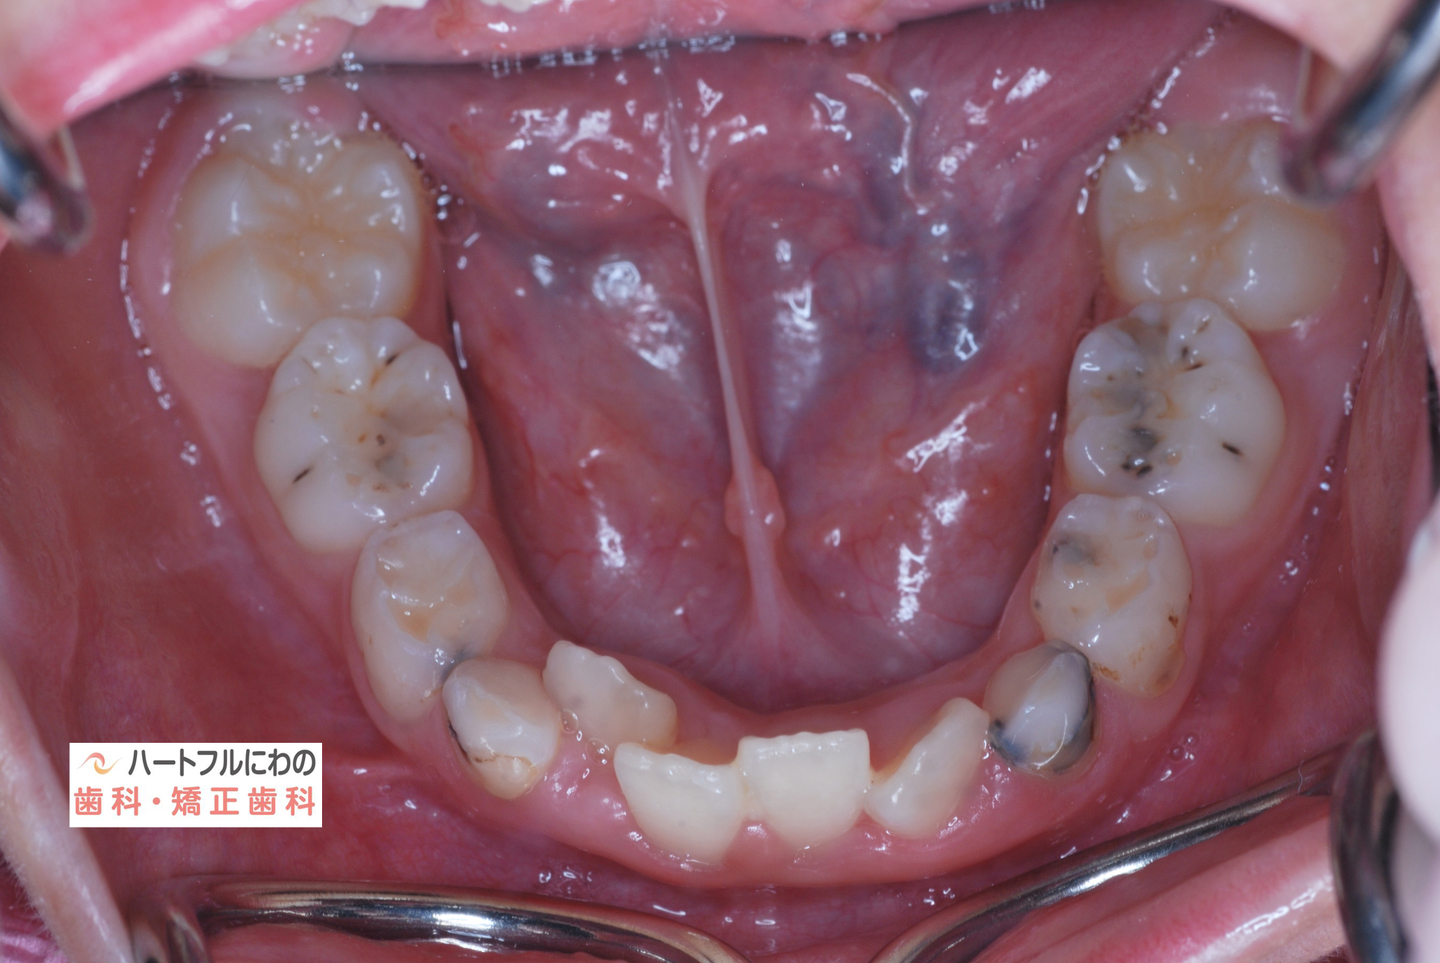

お口の中を拝見すると、上下の叢生(いわゆるガタガタ、乱ぐい)がみられ、多数の虫歯と歯肉炎がみられました。上唇小帯(上唇のすじ)の問題もありました。口呼吸で口腔内が乾燥すると通常の何倍も歯垢が付きやすくなり、虫歯や歯肉炎が頻発します。口呼吸の強い子は重なっている部分のかみ合わせが深い(下の歯がほとんどみえない)のもよく見られる特徴です。

その間に食事指導も含め、虫歯や歯周炎の管理も行います。このお子さんは炭酸を含む清涼飲料水が好物でその指導に苦労しましたが、初診時以降は虫歯の発症なく、思春期性の歯肉炎も軽度ですんでいます。